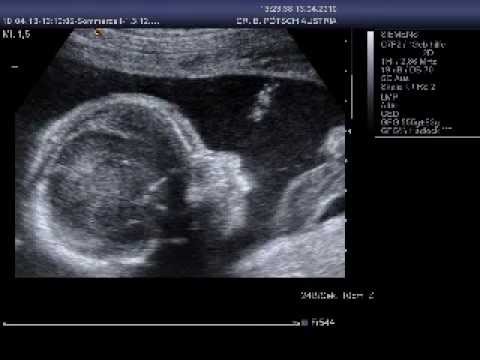

Sollten noch Befundergebnisse offen sein, oder sie sonst spezifische Fragen zu Verhütung, Schwangerschaft oder Medikamenten an Herr Dr. Pötsch haben, können sie uns gerne jederzeit telefonisch erreichen.